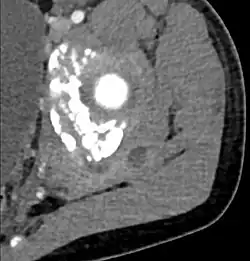

CT with IV contrast showing enlargement and heterogeneous hypodensity in the right pectoralis major muscle. A focal abscess collection with gas within it is present medially. There are enlarged axillary lymph nodes and some extension into the right hemithorax. Note the soft tissue and phlegmon surrounding the right internal mammary artery and vein. The patient was HIV+ and the pyomyositis is believed to be due to direct inoculation of the muscle related to parenteral drug abuse. The patient admitted to being a "pocket shooter" -